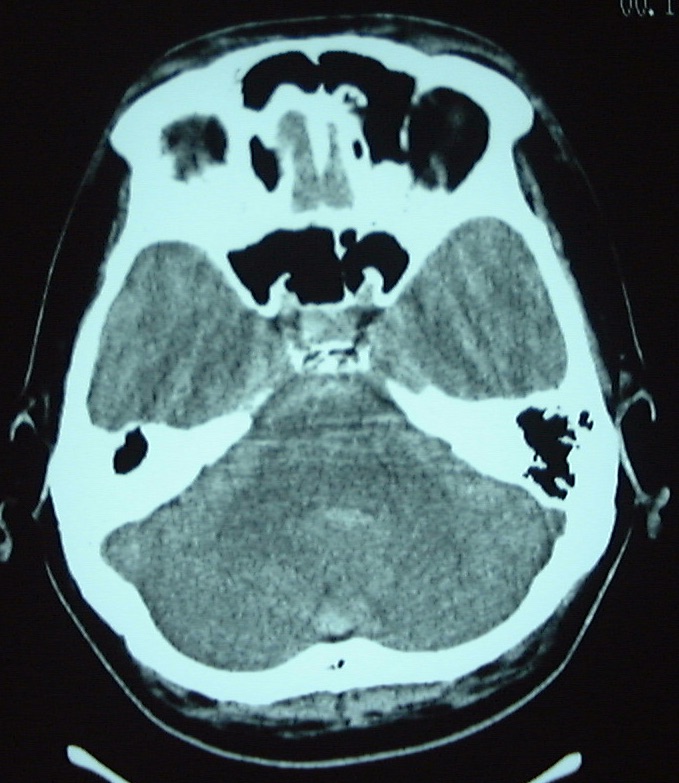

<入院時の頭部CT;くも膜下出血を認める>

<右解離性椎骨動脈瘤:矢印>